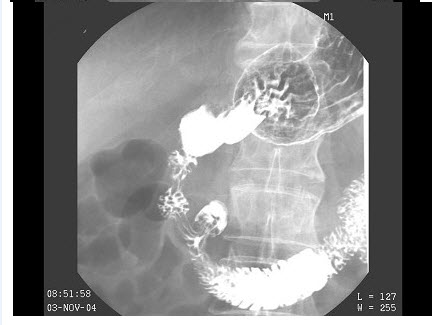

男,80岁,脐周隐痛反复发作半年,加重1月,体检:脐周压痛,以脐上为主,无反跳痛,结合图像,最可能的诊断为()

C、胃癌

D、笔杆征

E、降段憩室

E